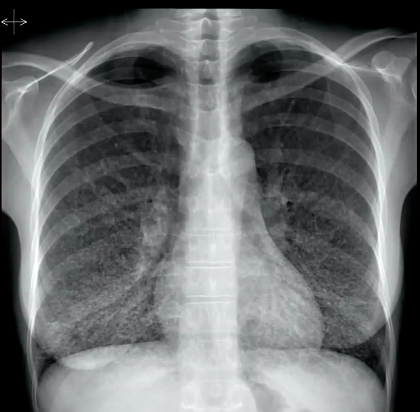

What pathology is shown?

Pericardial effusion from TB